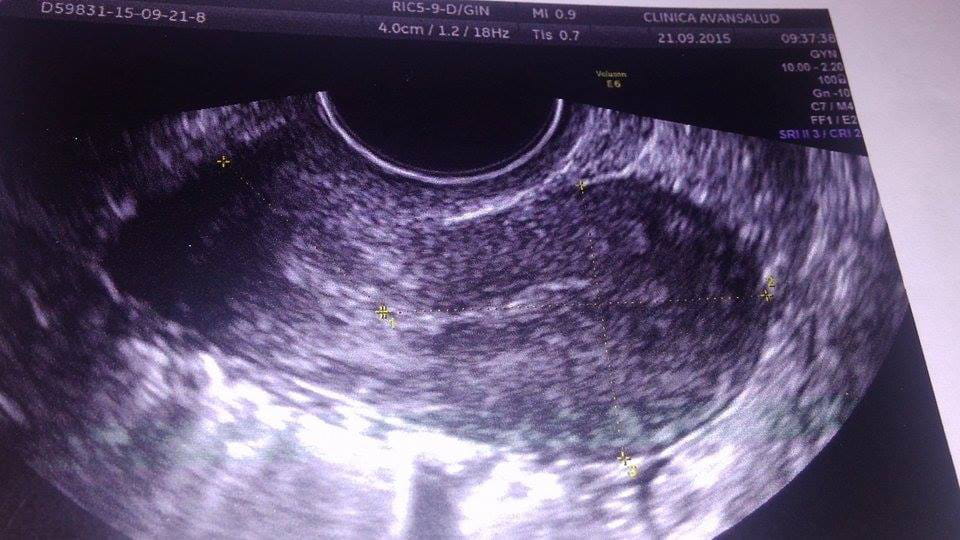

Hola, nunca habia escribido en algun foro pero lo q me conlleva a hacerlo son mis sintomas y creo estar embarazada pke lo digo pke hace un mes que no me llega la regla sufro de ovarios poliquisticos es normal que se me retrase pero esta vez de retraso siento asco presion en el vientre perp no una presion cualquiera sino q como q los musculos de mis ovarios estan estirandose algo asi siento un dolor en los senos perp tremendos no me puedo ni apoyar los senos en algun lado me eh sentido tan extraña hasta eh sentido vibracion en mis labios vaginales y se q solo le pasa alas personas embarazadas ... resulta q me hice una ecografia y sale esto miren creoo que es el saco gestacional ... perdonen mi ignorancia perp sera el saco gestacional mamis porfa respondanme me siento fatal con un dolor de estomago de utero de senos ... nose q pensar ... !

Eso es tu utero y tienes el endometrio delgado, por lo menos de momento en esa ECO no se ve EMBARAZO.... Pero se supone que eso sale en el informe de la eco no?